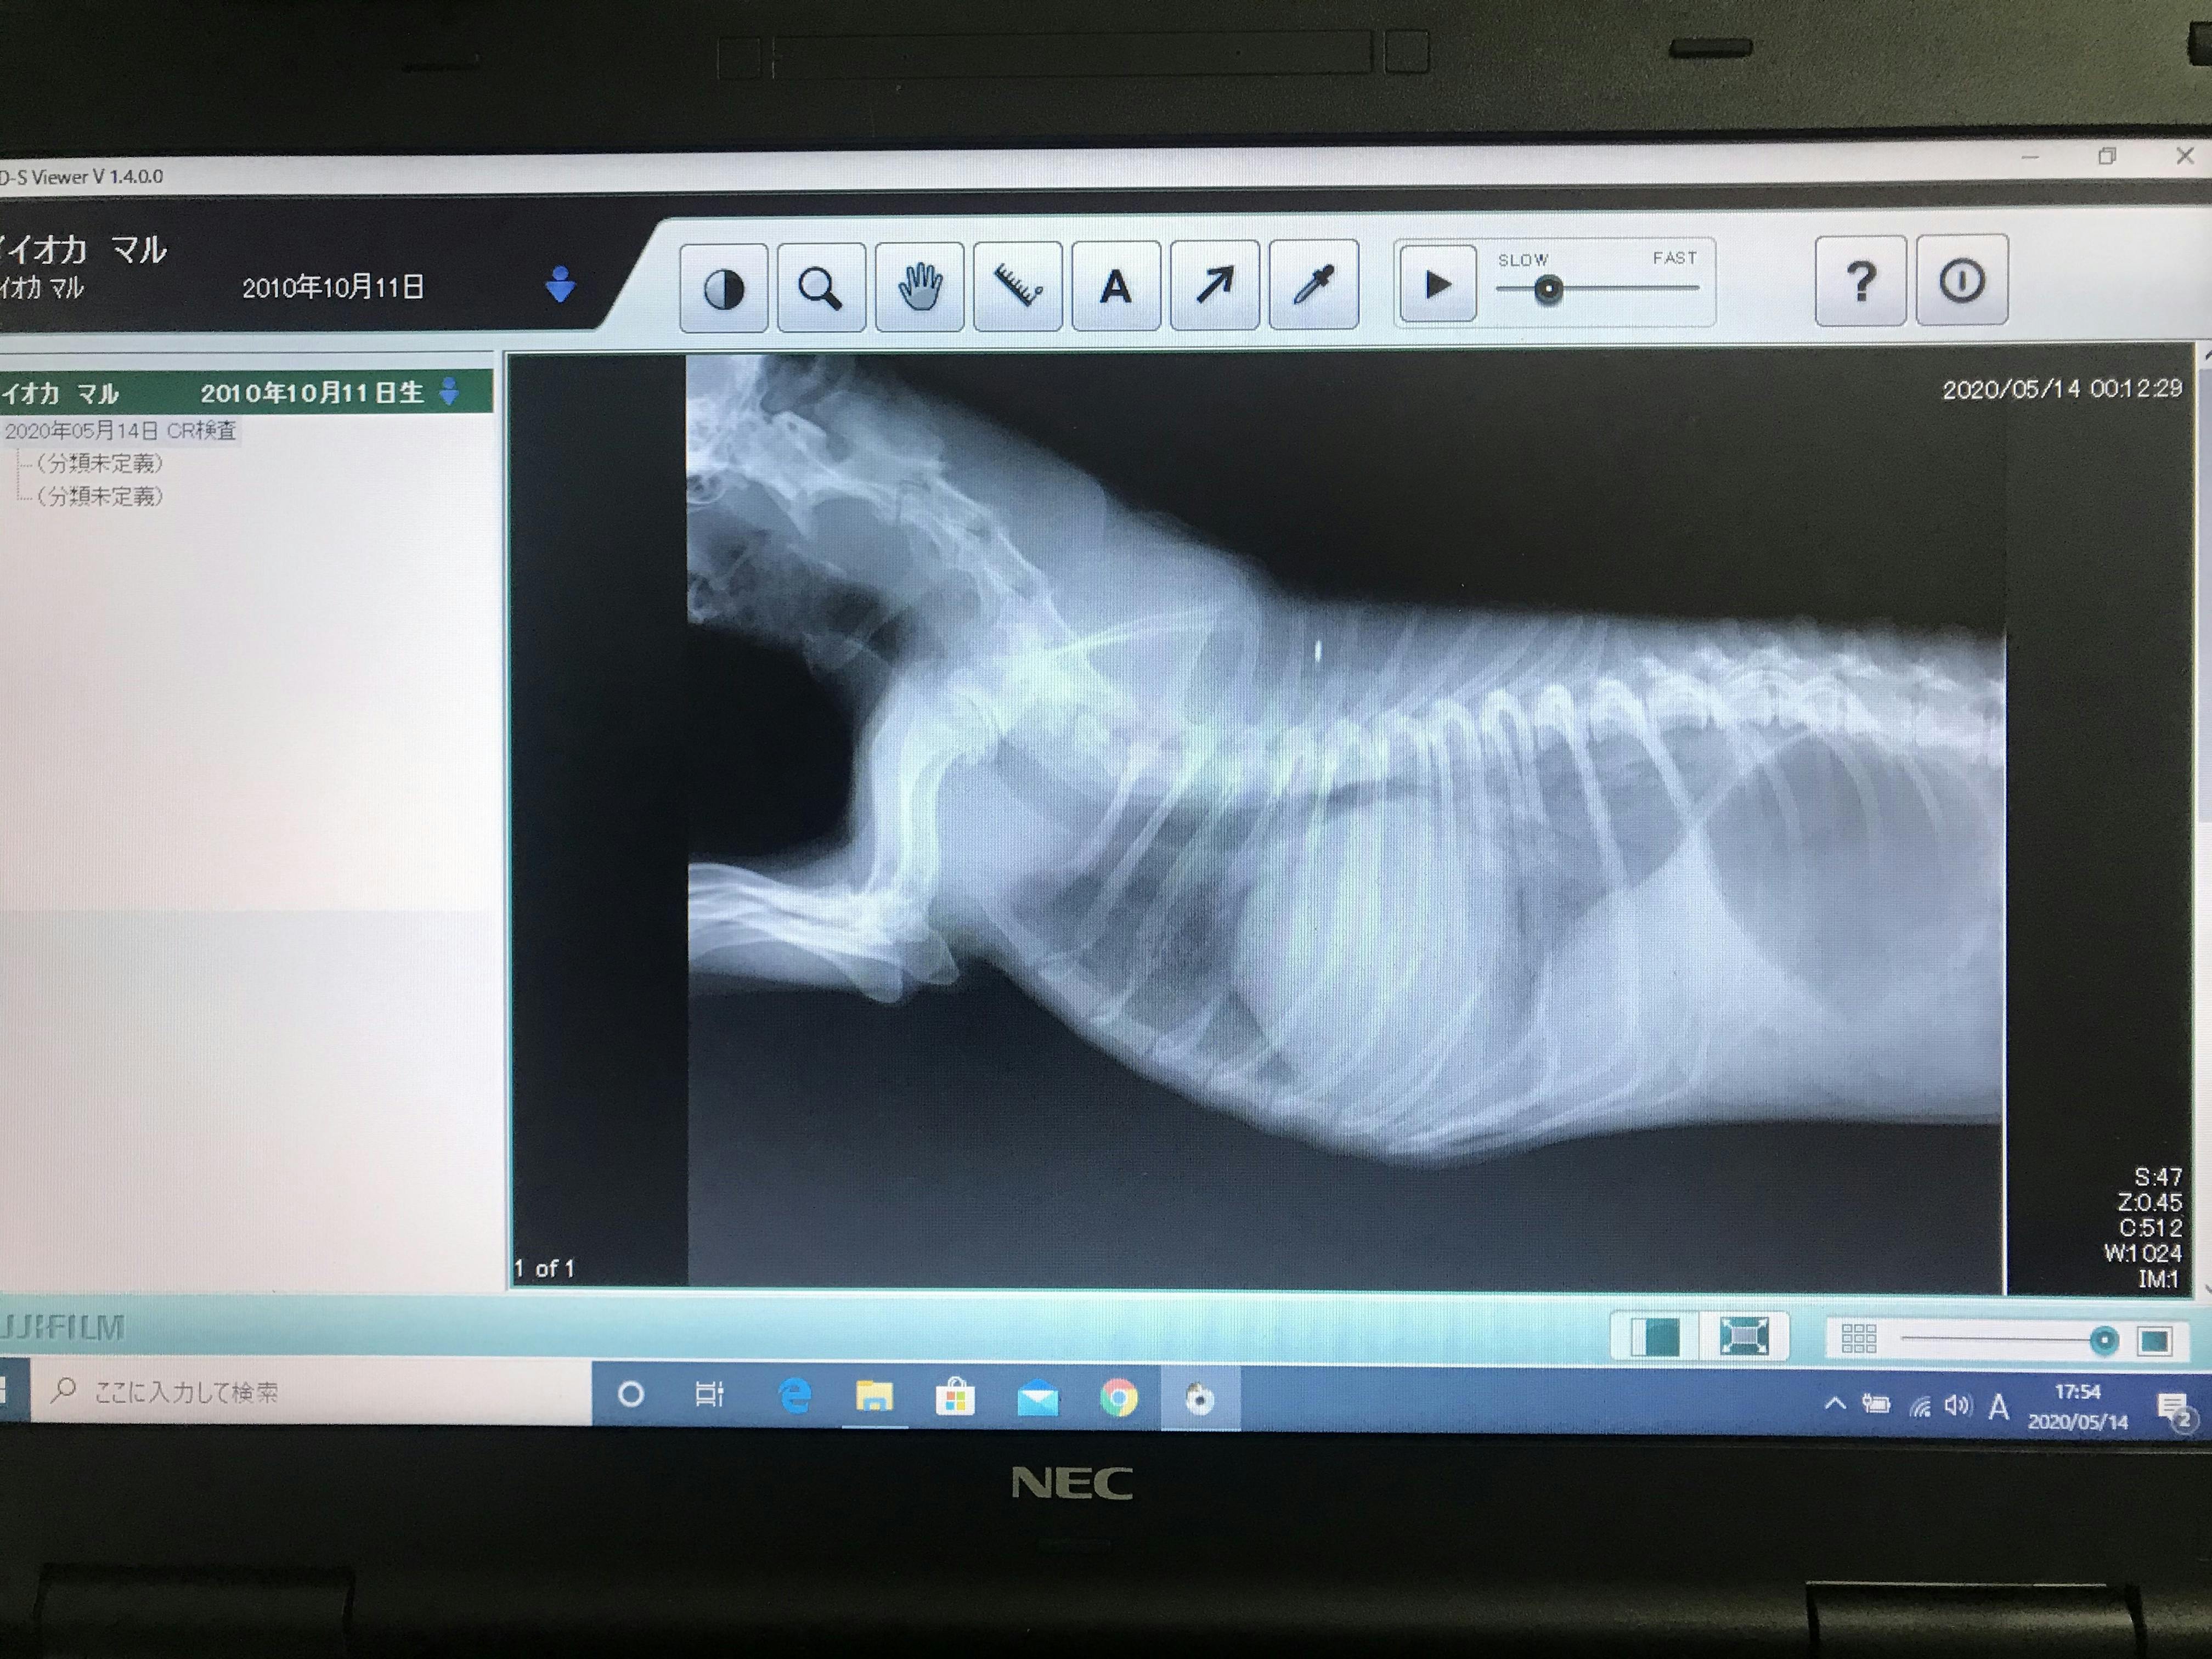

その時のレントゲンです。

肺の部分が真っ白で心臓肥大も尋常ではありません。